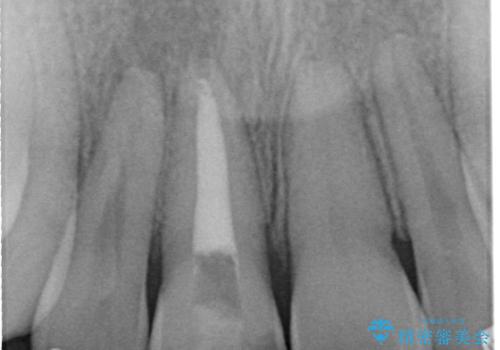

- 右上1番の色が暗いのを主訴に来院されました。

失活歯(神経の治療をしている歯)の場合、薬剤を歯の表面に塗布するホワイトニングでは白くなりません。歯の中に薬剤を入れて薬剤の反応を待つ必要があります。

治療手順としましては、マイクロスコープ(歯科用顕微鏡)を使用し、元々入っていた詰め物のCR(プラスチック)を除去します。その後、歯の中に薬剤を入れ、蓋をします。2週間後に来院して頂き、白くなっているかを確認します。ご本人がご満足頂く白さになるまで、これを3~4回繰り返します。今回は1回で患者様がご満足されたので治療を終了しています。

精度を高めるために当院はマイクロスコープを使用しています。